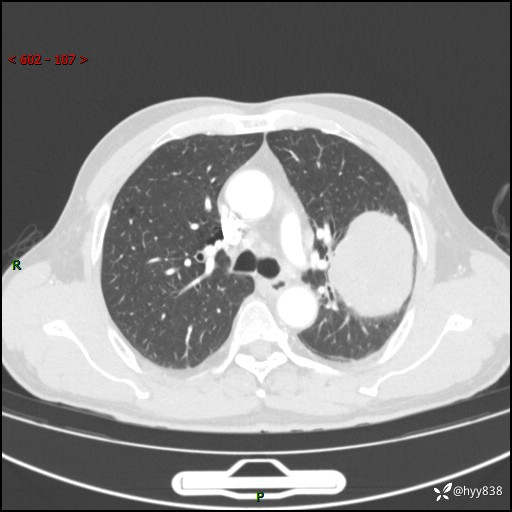

68岁/男,发现左下肺占位5天。如此大的肿块,患者竟然没有症状---结果公布~

【患者信息】:68岁/男

【主诉】:检查发现左下肺占位5天。

【现病史及既往史】:患者于4天前外院行“经尿道钬激光碎石术”,住院期间胸部CT检查发现左下肺肿块,患者平素无明显咳嗽咳痰,无心慌、胸闷、胸痛、呼吸困难、低热、盗汗,无头痛、头晕,无腹痛、腹胀等不适,现患者为求进一步治疗,遂来我院就诊,以“左下肺肿块”收入我科。 患者自起病以来,精神可,睡眠可,饮食可,大小便正常,体重无明显改变。

【检查】:胸部CT增强扫描